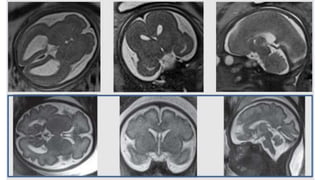

TRANSTORNOS DE ORGANIZACIÓN

27ss

26ss

TRANSTORNOS DE MIGRACIÓN:HETEROTOPIA (CORTICAL – PERIVENTRICULAR)